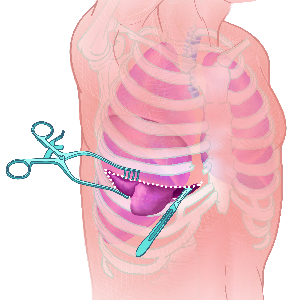

Detailreiche Fotografien aus der medizinischen Praxis ergänzen die Texte; moderne, genaue,

wissenschaftliche Zeichnungen geben Einblick in die Anatomie und die Funktion der Lunge und

anderer Organe.